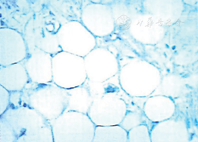

女性,45岁,因"体检发现后纵隔占位6 d"于2015年4月13日入院。查体无明显异常。实验室及器械检查显示:胸部CT显示右后纵隔内可见一较大不规则形异常密度影,最大横断面范围约160 mm×103 mm,内部密度混杂多样,可见多发脂肪成分及钙化灶,见多发分隔及多囊性病灶。增强后病变部分可见强化,部分未见强化,纵隔内心脏、血管、支气管及食管可见明显受压推移改变;纵隔、肺门未见肿大淋巴结影,右侧胸腔可见积液,胸膜未见增厚,考虑畸胎瘤(图1)。心电图示窦性心律,正常心电图。上消化道造影示食管中下段被纵隔右后方块状物推移至左侧;食管黏膜光整,形态规则,蠕动正常(图2)。肺功能检查显示:用力肺活量(forced vital capacity,FVC)为2.21 L,占预计值的77.2%;第1秒用力肺活量(forced vital capacity in the first second,FEV1)为1.79 L,占预计值的74.8%;最大通气量(maximum ventilatory volume,MVV)为86.52 L/min,占预计值的103.2%;FEV1/ FVC%为80.8%,提示肺功能轻度损害,混合性肺通气功能障碍。心脏彩超显示:心脏结构及功能未见明显异常。血常规、肝肾功能、凝血功能、血液传播疾病检查示基本正常。2015年4月20日,患者在双腔气管插管下行静脉复合麻醉,采用右胸后外切口从第6肋上缘进胸,术中见心脏后方巨大囊实性纵隔肿瘤,约18 cm×17 cm×10 cm,占据右后半胸腔。右下肺受压,部分粘连。肿瘤与主动脉、左下肺、右下肺、左右主支气管、食管、膈神经关系紧密,与两侧下肺均有粘连。手术切除完整的具有包膜多结节状肿物(图3)。切面灰白实性,呈鱼肉状,质地中等,界限清。病理诊断:高分化型脂肪肉瘤(图4)。患者病情恢复良好,术后第14天出院。